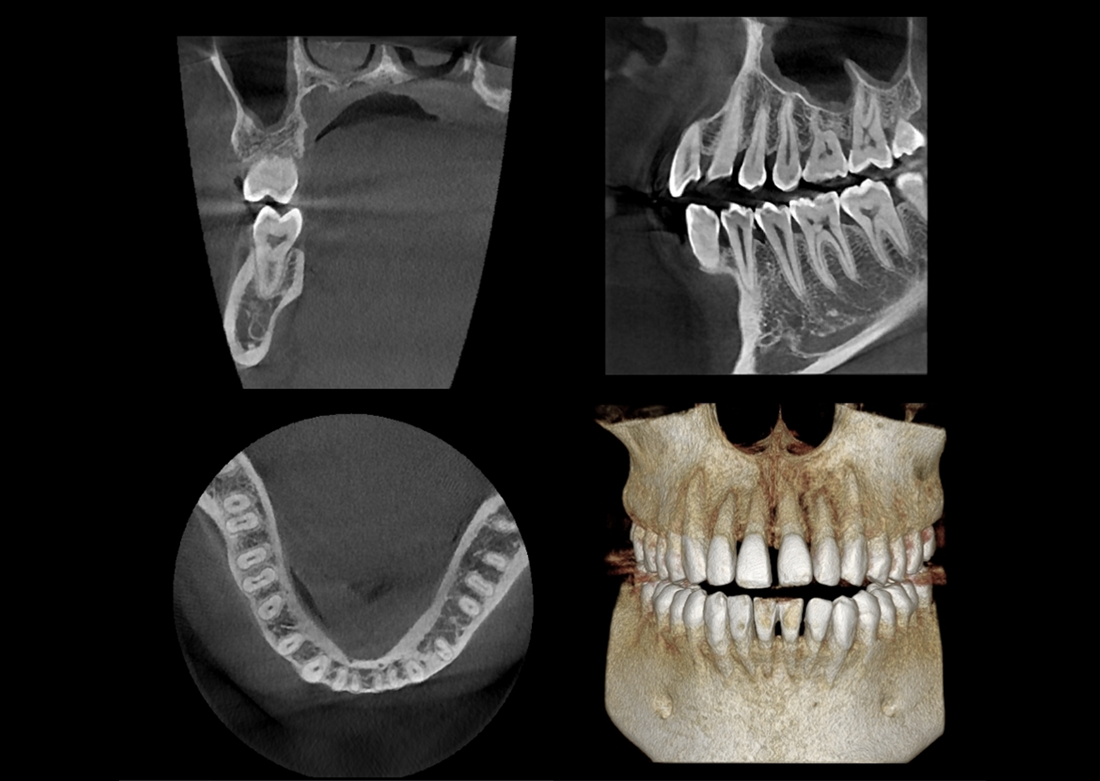

The Papaya 3D Premium/Ultra is the newest generation in a long line of Genoray products designed to produce accurate diagnostic images with wider treatment applications including implants, endo, ortho, airway, TMJ, and orthognathic surgeries. Optimized acquisition PC/Monitor/Accessories, model scan/STL converter, and perpetually licensed software suites included.

- Papaya 3D Premium CBCT: Min 4x5 to Max 16x14 FOV

- Papaya 3D Ultra CBCT: Min 4x5 to Max 23x24* FOV